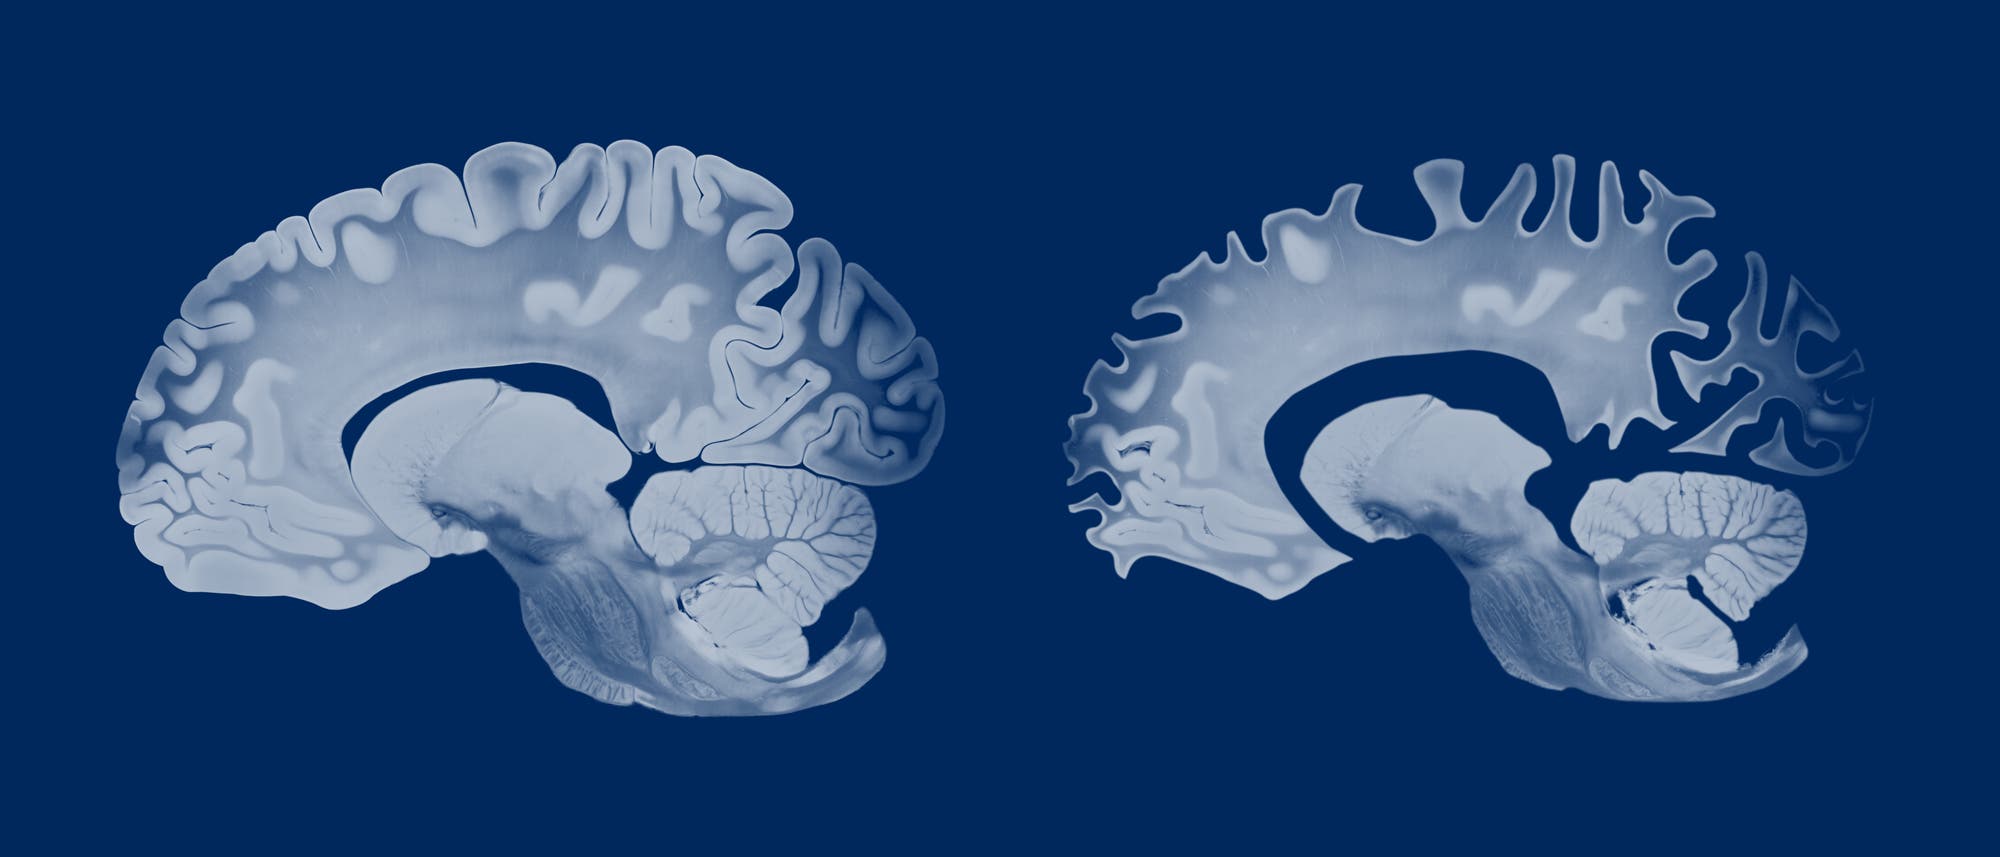

Ab Mitte 30 beginnt das Gehirn zu schrumpfen. Mit neurodegenerativen Erkrankungen wie Alzheimer hängt dieser normale Alterungsprozess aber offenbar nicht zusammen. Dabei nimmt das Hirnvolumen deutlich drastischer ab (im Bild rechts).

Die Alzheimerkrankheit geht ebenfalls mit einer Hirnschrumpfung einher, wenn auch in deutlich drastischerem Ausmaß. Man könnte daher annehmen, dem normalen altersbedingten Rückgang des Hirnvolumens und der Atrophie durch Alzheimer würden vergleichbare Ursachen zu Grunde liegen. Da Frauen statistisch gesehen deutlich häufiger von der neurodegenerativen Erkrankung betroffen sind, müsste in dem Fall das weibliche Gehirn stärker vom Volumenrückgang betroffen sein als das männliche – insbesondere jene Hirnregionen, die durch Alzheimer am schnellsten geschädigt werden, wie der Hippocampus. Die Studie ergab aber das Gegenteil, weshalb die Fachleute davon ausgehen, dass die strukturellen Veränderungen im Alter auf andere Prozesse zurückgehen als jene bei Demenz.